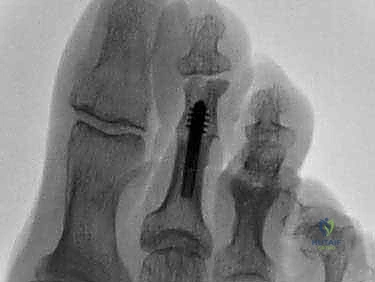

ب. تثبيت المفصل (Arthrodesis - Joint Fusion)

يُعتبر هذا الإجراء المعيار الذهبي لحالات إصبع القدم المطرقية الصلب جداً والمؤلم، أو الحالات المرتجعة. يقوم الدكتور هطيف بإزالة الغضروف التالف من نهايتي العظمتين المكونتين للمفصل الأوسط (PIP)، ثم يتم دمج العظمتين معاً لتكوين عظمة واحدة صلبة ومستقيمة.

* الميزة: يوفر استقامة دائمة وقوية للإصبع، ويقضي على الألم تماماً لأنه يمنع أي حركة في المفصل التالف.

* طرق التثبيت: تقليدياً، تُستخدم أسلاك كيرشنر (K-wires) التي تبرز من طرف الإصبع وتُزال بعد عدة أسابيع. ولكن، مع التقدم التكنولوجي، يستخدم الدكتور هطيف في كثير من الأحيان غرسات داخلية حديثة (Intramedullary Implants) أو براغي دقيقة جداً تبقى داخل العظم، مما يجنب المريض إزعاج الأسلاك الخارجية ويسرع من عملية التأهيل.